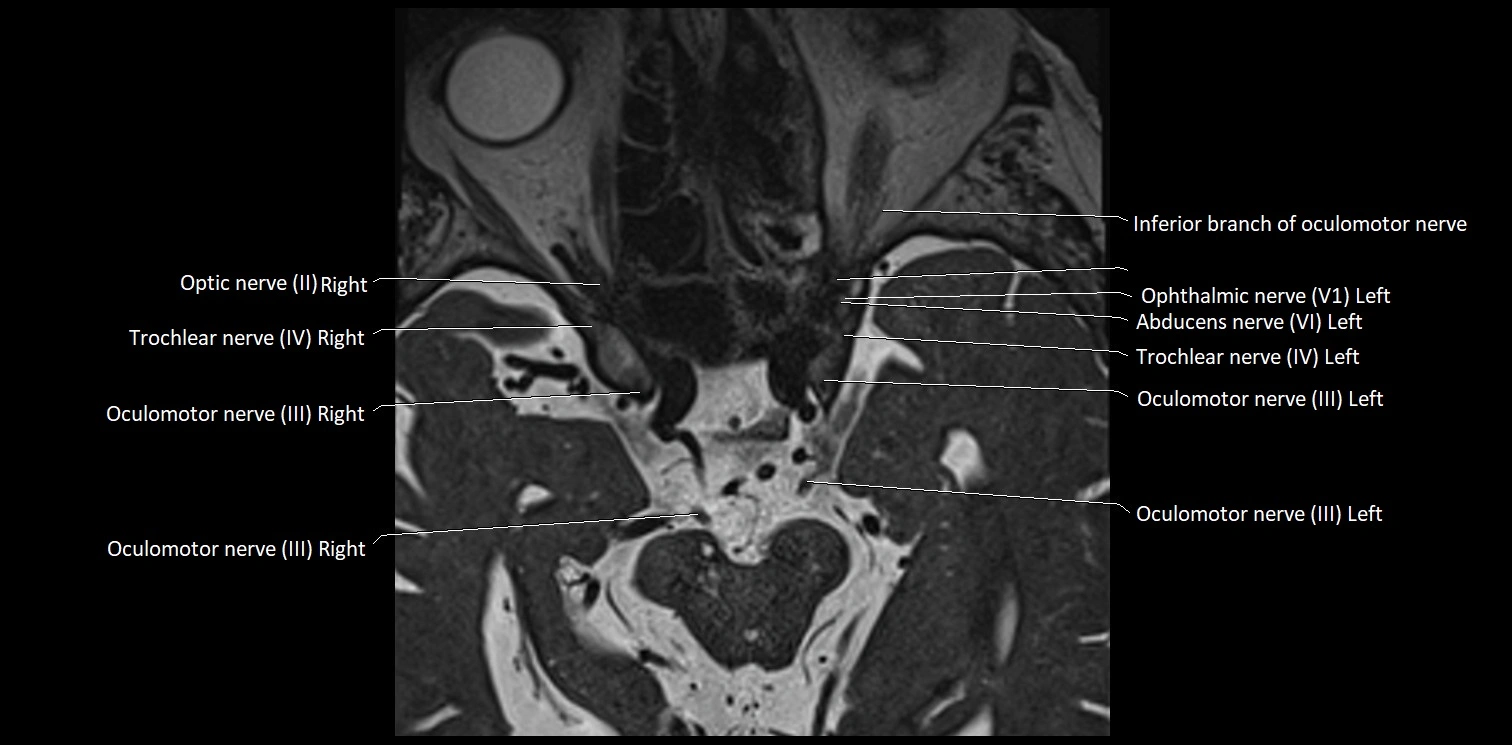

MRI images

image